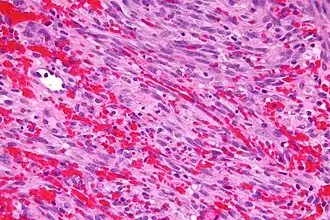

Herpesvirus humano 8 (HHV-8) ou Herpesvirus associado ao Sarcoma de Kaposi (KSHV) é um oncovírus DNAds , da subfamília herpesvirus gamma, associado com três tumores: Sarcoma de Kaposi, linfomas e doença de Castleman multicêntrica em pacientes com AIDS/SIDA.[1]